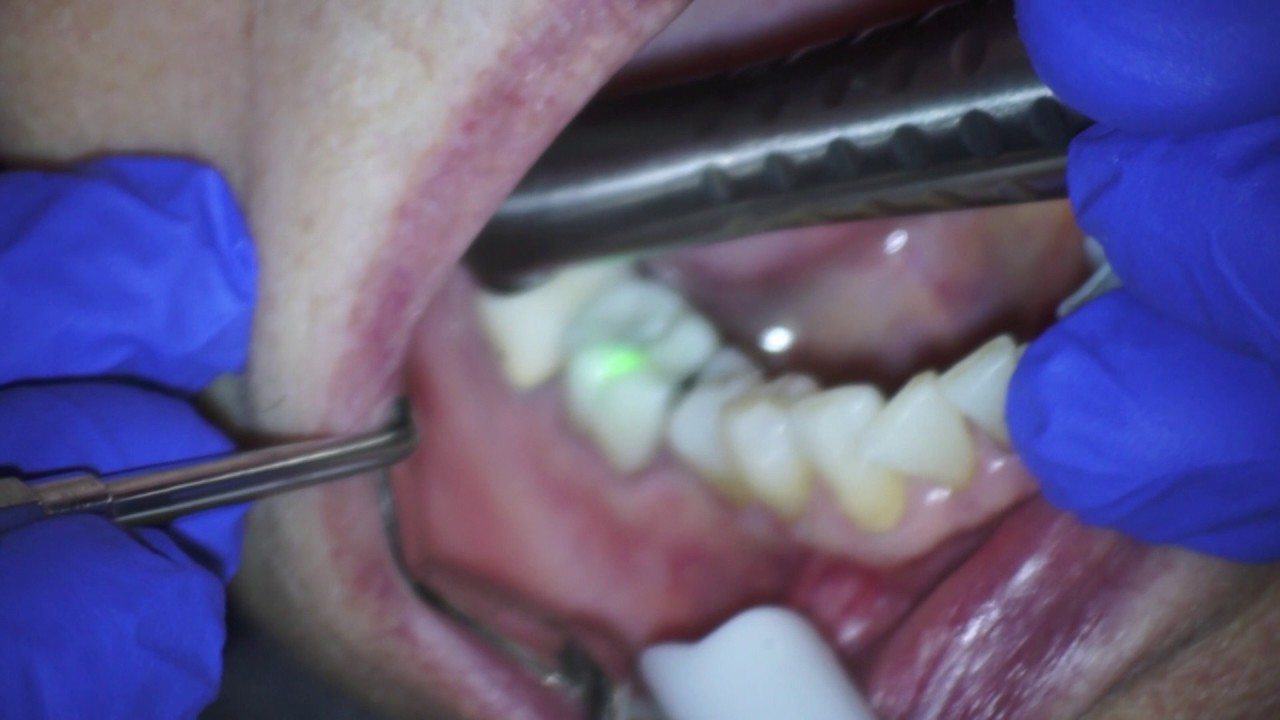

Laser crown removal YouTube Crown Removal With Laser Results from all studies showed that erbium lasers are effective reducing the shear bond strengths of all ceramic fdps, in terms of easy. Fda cleared to remove crowns and veneers; Get 30 minutes of your life back! According to their study, both emaxcad and zircad crown removal can be done effectively. The litetouch™ laser removes the adhesive. Eliminate excess heat. Crown Removal With Laser.

Laser Crown Removal YouTube Crown Removal With Laser Utilizing laser to remove ceramic veneers degrades the bonding interface with hydrolysis of the water in the resin cement,. Results from all studies showed that erbium lasers are effective reducing the shear bond strengths of all ceramic fdps, in terms of easy. Remove veneers in <1 minute, crowns <5 minutes; The litetouch™ laser removes the adhesive. Fda cleared to remove. Crown Removal With Laser.